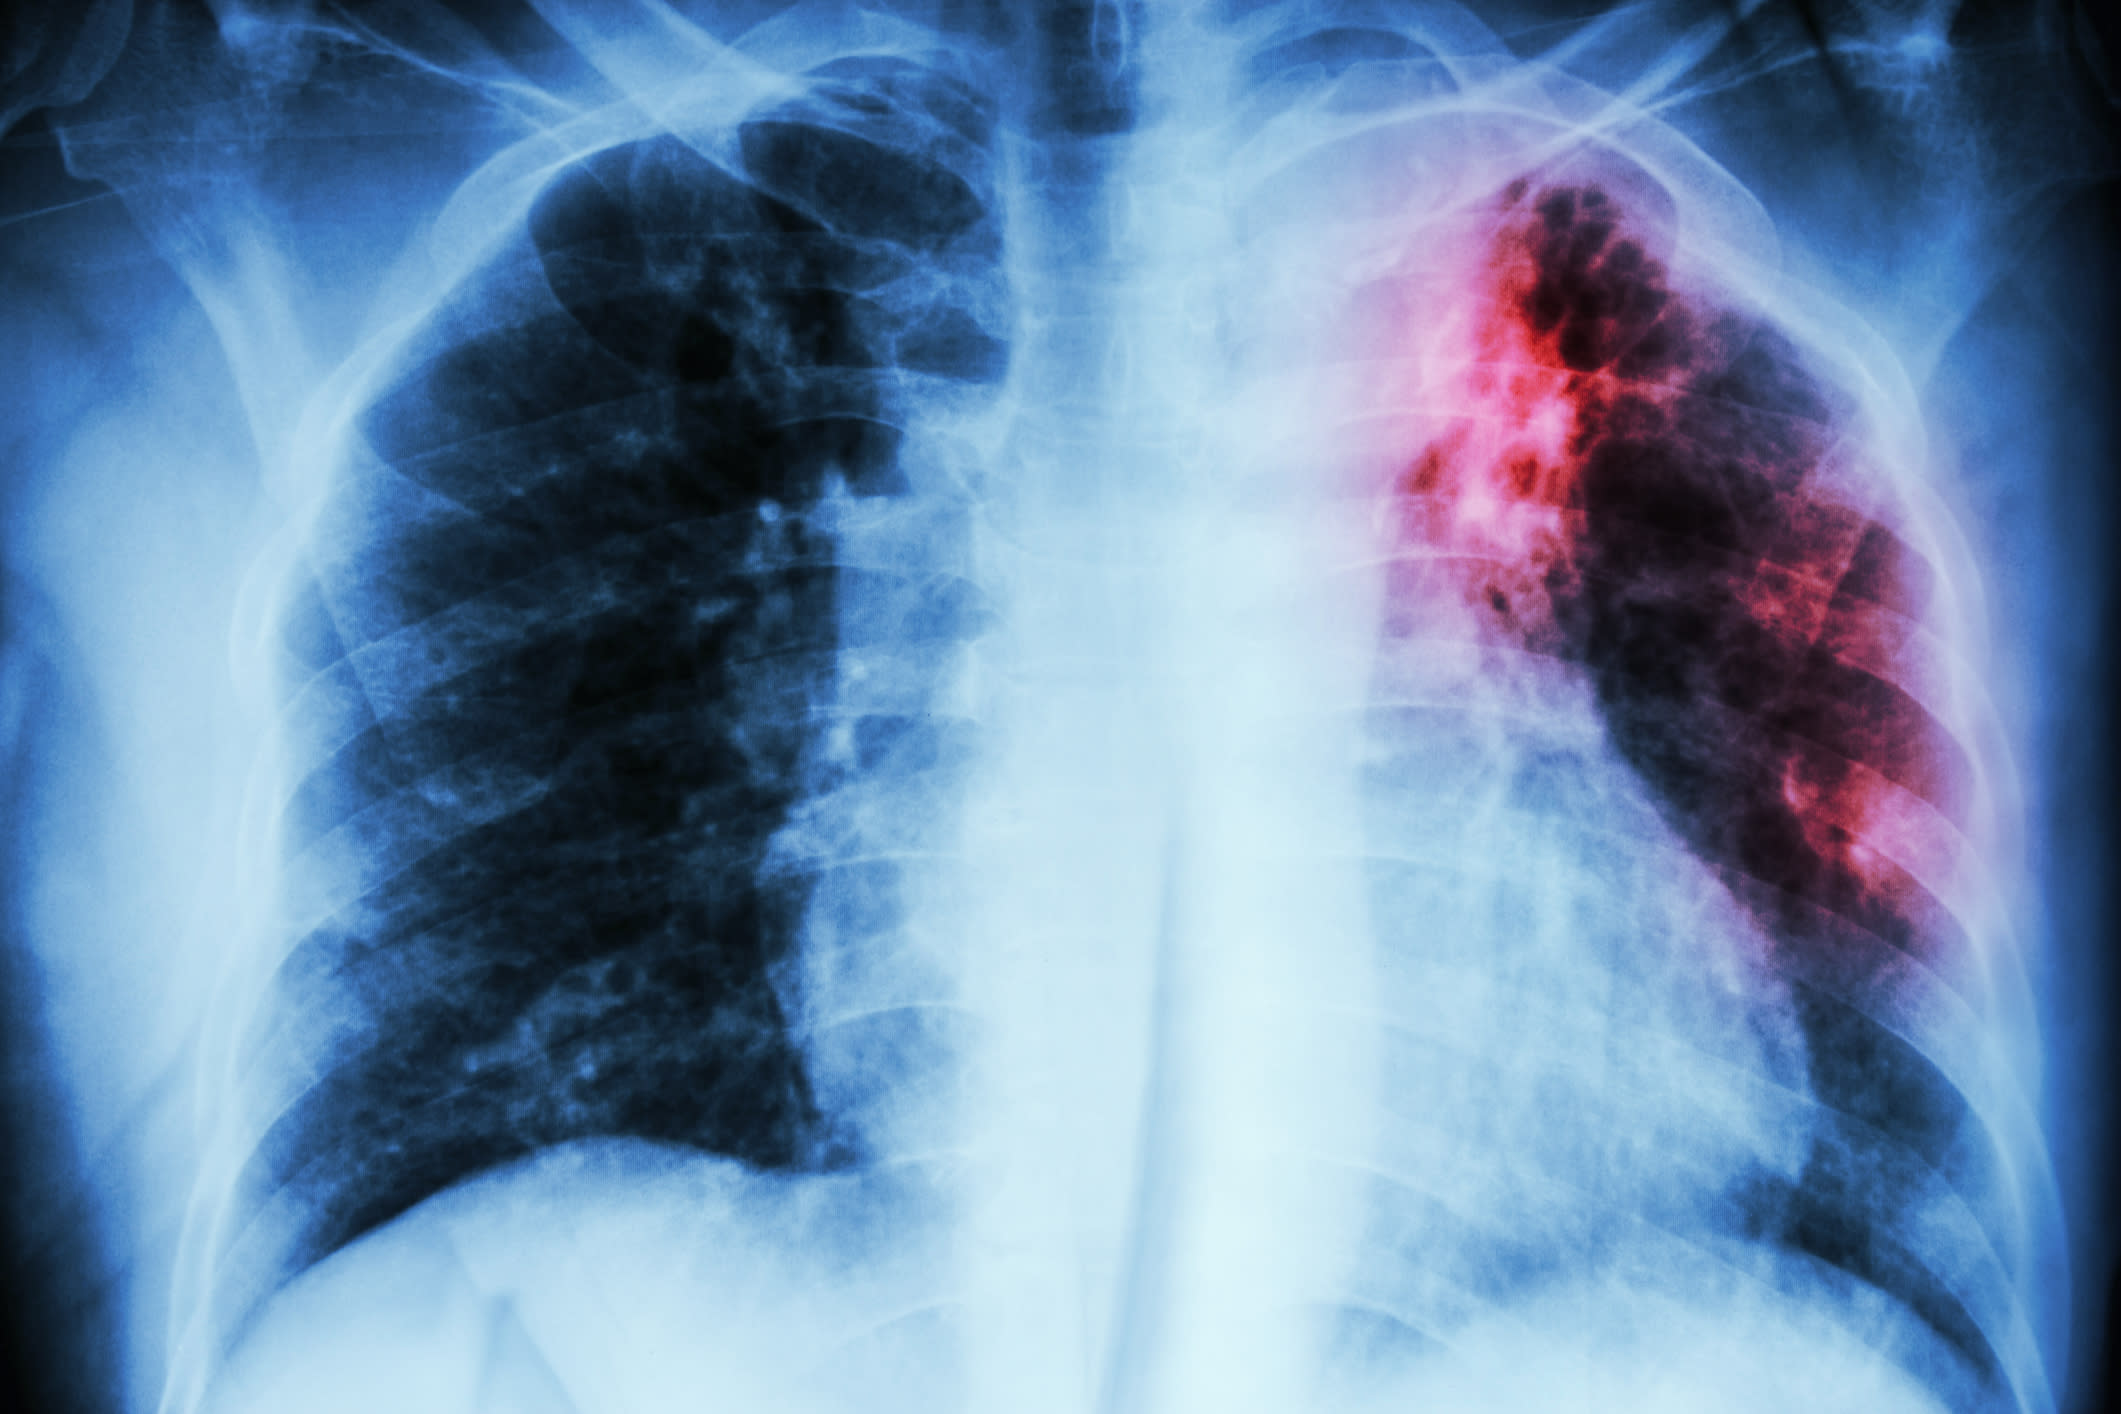

TB poses particular challenges since the emergence of XDR TB – extensively drug-resistant tuberculosis – which has survival rates similar to tuberculosis before the antibiotic era. People with drug-resistant TB are commonly isolated from the general population, and they sometimes end up “in prison-like conditions”.

Although TB is transmissible via casual contact, it is not highly contagious; it's largely a disease of poverty.

“TB infection usually results from long-term repeated exposure. If you live in crowded conditions with poor ventilation – and especially if you have bad nutrition – then you're more likely to get it,” Professor Selgelid says.